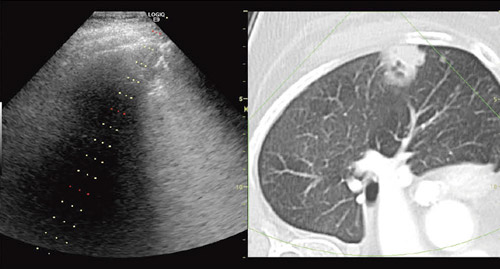

図1にImage Fusionの一例を示す。画面の左側には超音波のリアルタイム画像が表示され,右側には超音波画像の断面位置に対応したCT画像が同期表示され,両者の画像が容易に比較参照できるようになっていることが理解される。参照画像として表示されるCT画像は,あらかじめDICOMで保存されたデータを記録媒体もしくはネットワーク経由で,超音波診断装置上にダウンロードされている必要がある。

図1 超音波とCT,MRIのフュージョン表示

図6は肺への適用である。臓器としての肺は中空であり,超音波にとって適用が難しい領域の1つである。体表から肺へ穿刺を行う場合,気胸が伴うために非常に慎重な対応が必要になる。このような場合でも,もし,腫瘍が肺の体表近傍にあれば,CT画像を参照としたVolume Navigation機能を用いることにより,超音波ガイド下でより安全に穿刺が可能となる。

図6 肺への適用例